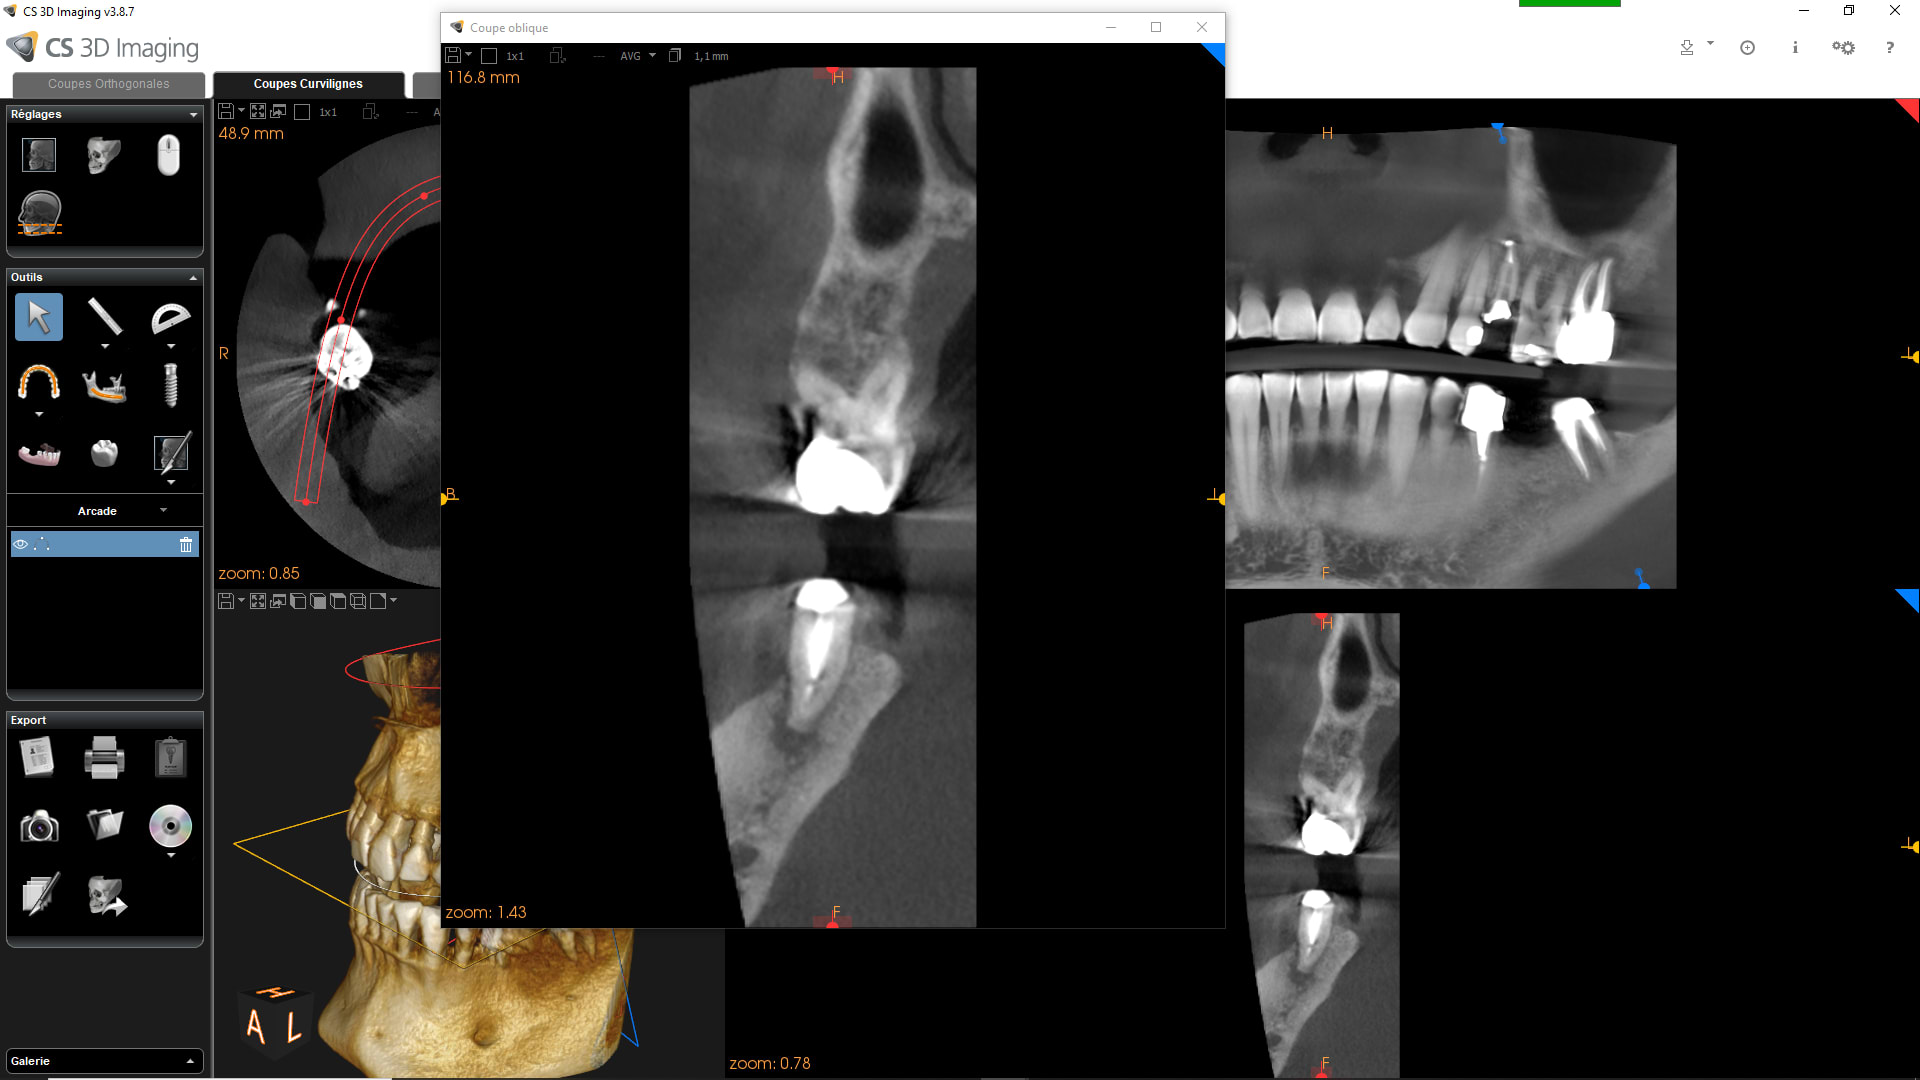

Effectivement première fois que cela m'arrive en 35 ans d'exercice !!

Traitement canalaire de la 47: la pâte à canaux ( Sealite Ultra ) a fusé au dela de l'apex lors de l'obturation à la guttachaude. Malheureusement le canal dentaire passe juste au niveau de l'apex et la pâte est rentré à l'intérieur.

La patiente n'a eu aucun signe pendant 3 jours puis paresthésie au niveau mentonnier ( pas au niveau labial) . La patiente décrit cela comme une fin d'anesthésie.

Quelles sont vos avis sur la récupération de la sensibilité ?

Depuis 3 semaines la paresthésie n'a pas changé ( diminué ou augmenté) .

19/01/2020 à 19h24

Désolé pour les images cone beam: je n'arrive pas à les mettre dans le bon sens!!